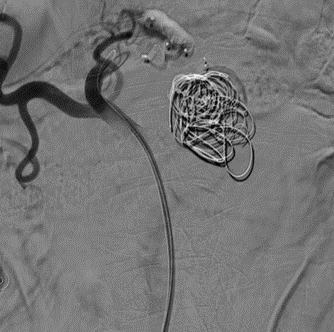

手术过程(二):使用Ⅱ型AVP栓塞载瘤动脉远端,弹簧圈栓塞脾动脉瘤瘤体,但瘤体巨大,弹簧圈略显不足

图片

手术过程(三):Ⅳ型AVP直接栓塞载瘤动脉近端,仍有部分侧枝显影